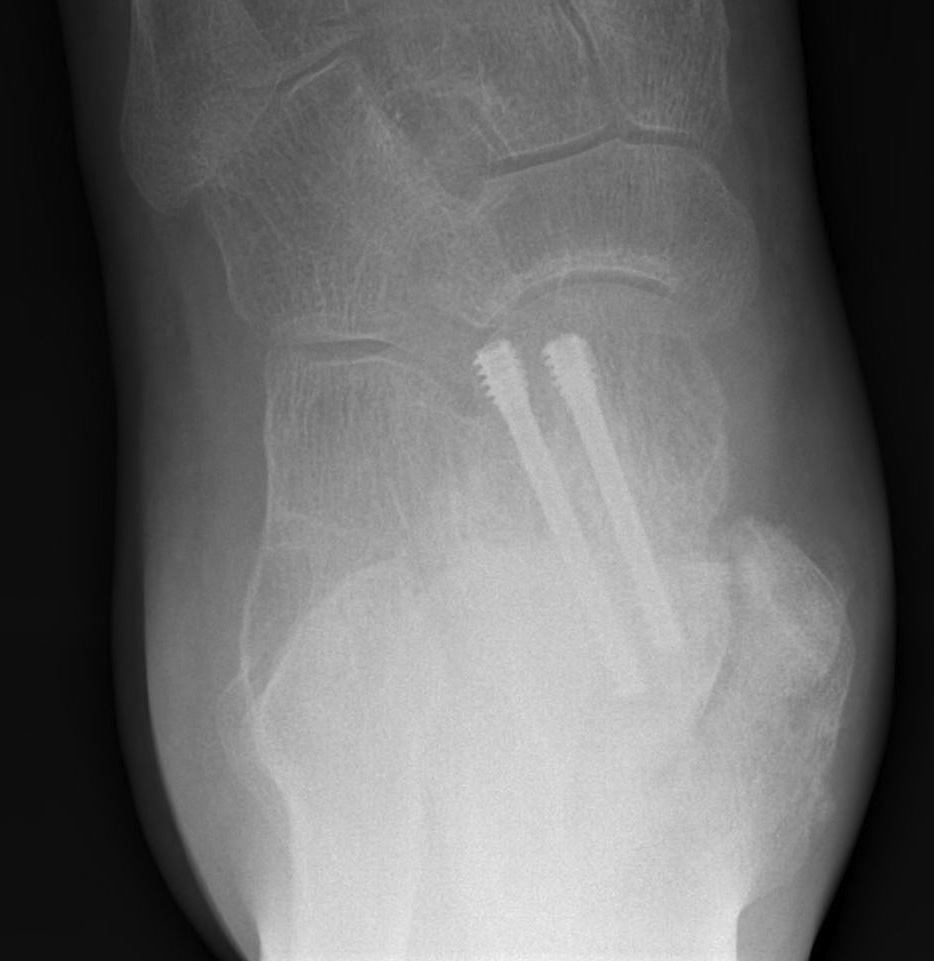

Canale view

- evaluates talar neck

- foot everted 15 deg

- look for medial shortening / varus

Cannulated screws

Xrays

| AP | Lateral | Canale View |

|---|---|---|

| Entry point of the screws |

Evaluate neck reduction

|

Evaluates the neck reduction |

Lateral off articular surface Medial through articular cartilage |

Depth of screws |

Beam angled 75o to foot Foot 15o pronated |

AP, Canale and Lateral xray